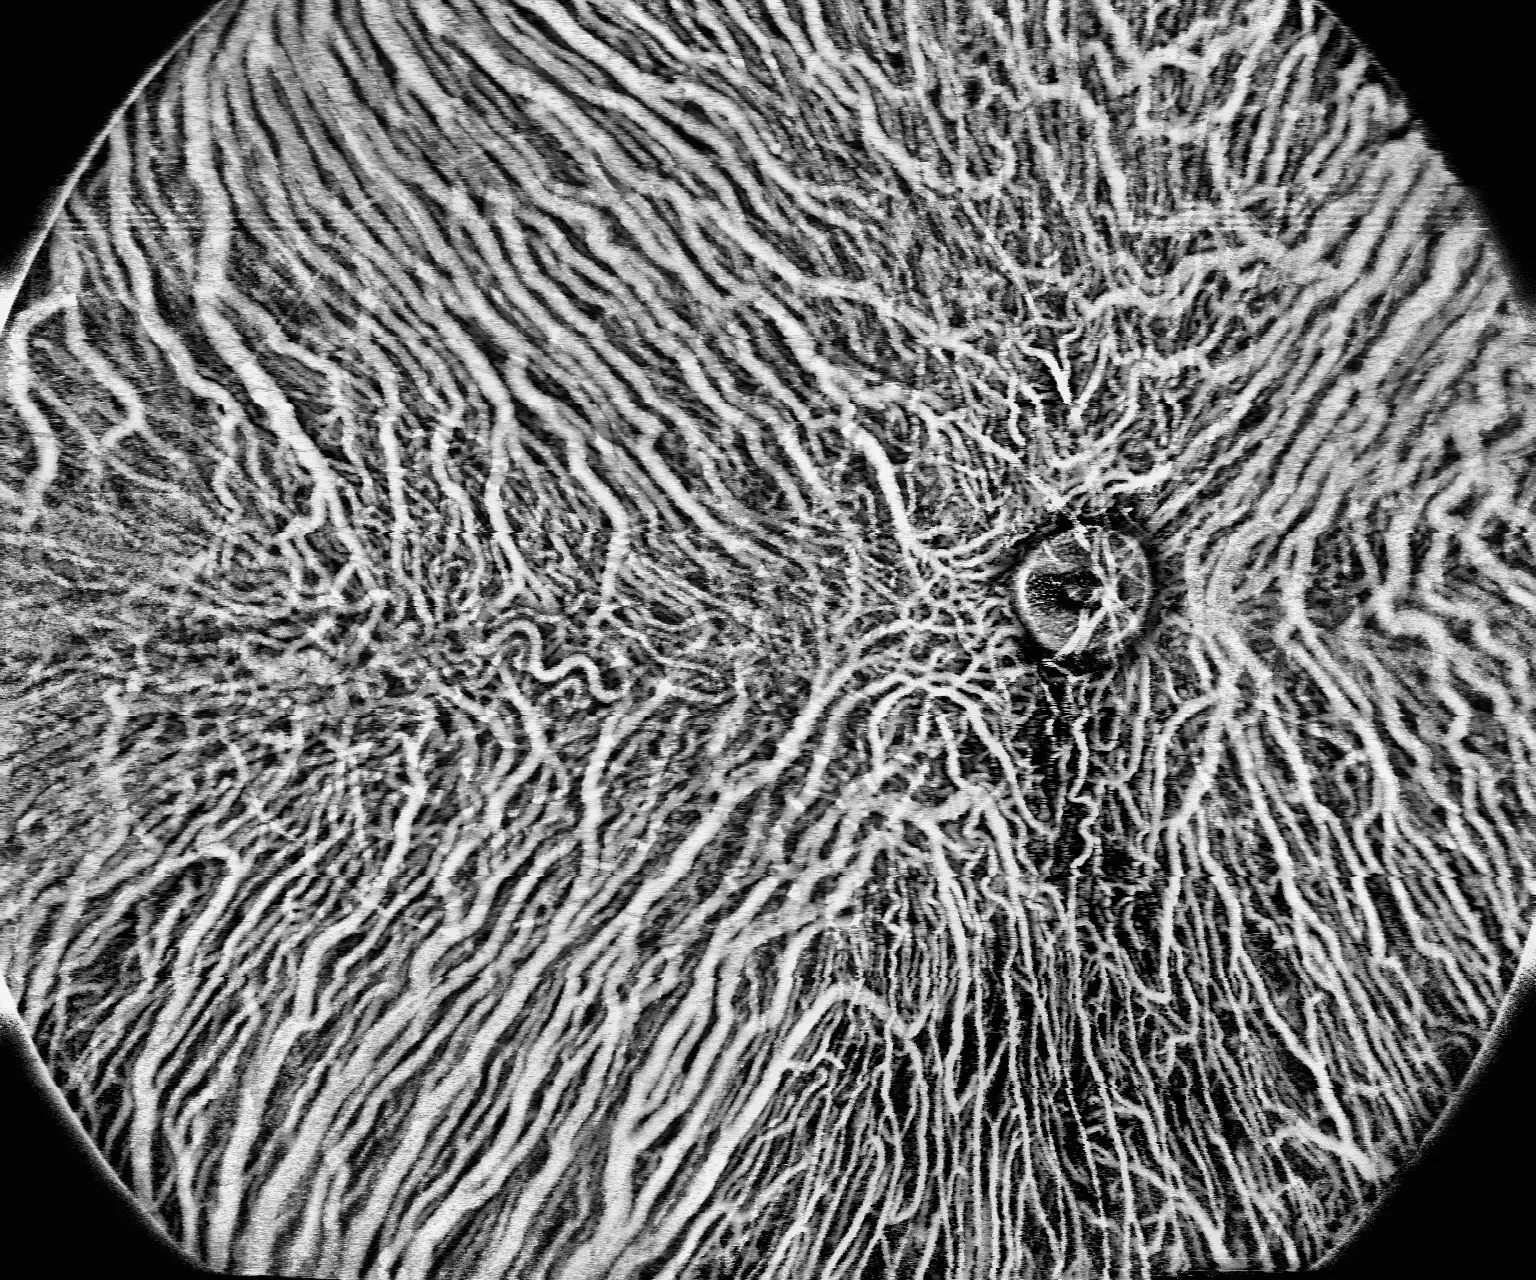

Umożliwia obrazowanie OCTA w zakresie 24×20mm, co pozwala na wykrywanie patologii obwodowych siatkówki, wcześniej niedostępnych dla standardowych systemów.

Ultra-szerokokątne obrazowanie 24×20mm wykrywa zmiany obwodowe siatkówki

BMizar umożliwia diagnostykę patologii w obszarach siatkówki niedostępnych dla standardowych systemów OCT. Dzięki rekordowemu polu widzenia placówka może wykrywać wczesne stadia retinopatii cukrzycowej, obszary niedokrwienia i neowaskularyzację obwodową, co przekłada się na lepsze wyniki leczenia pacjentów i buduje reputację ośrodka jako centrum diagnostycznego najwyższej klasy.

Ultra-szerokokątne obrazowanie 24×20 mm umożliwia wykrywanie zmian obwodowych siatkówki niedostępnych dla standardowych systemów OCT